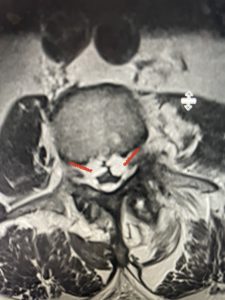

(Figs 3a) Sagittal (a) and Axial (b) T2-weighted lumbar MRI demonstrating severe spinal stenosis L2-5 (arrow)and extruded disc at L3-4 on axial image (arrow)

(Fig 3b)